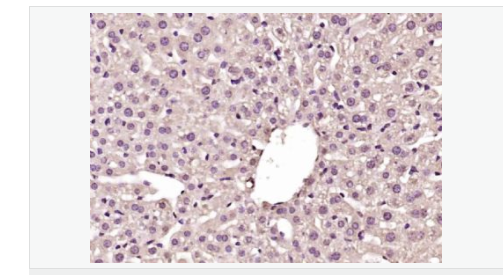

| 產品應用 | WB=1:500-2000 ELISA=1:5000-10000 IHC-P=1:100-500 IHC-F=1:100-500 IF=1:100-500 (石蠟切片需做抗原修復) not yet tested in other applications. optimal dilutions/concentrations should be determined by the end user. |

| 細胞定位 | 細胞核 |